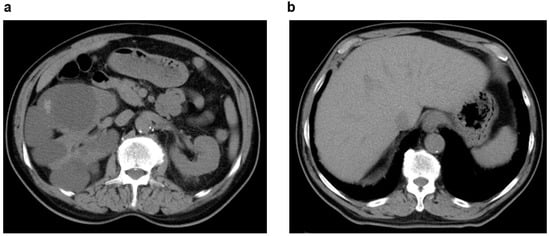

2.1. Multiple Simple Renal Cysts